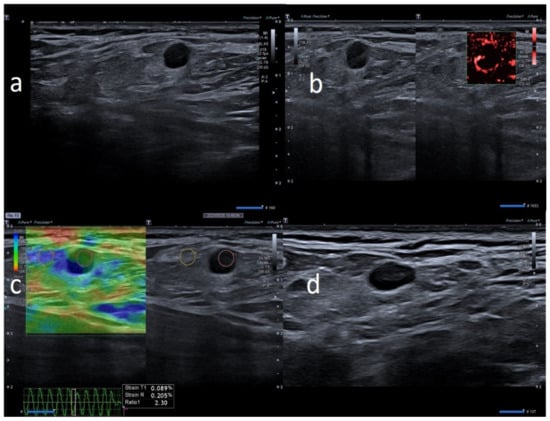

| M | 42 | Pfizer | Axillary ipsilateral to vaccine injection | Occasionally 1 weeks after second dose during chest ct | None | 3 | Variable: from 1.5 to 2.0 cm | Ovular | Simmetric cortical thickening with normal hilum | Stiffness similar to surrounding tissue | Normal | Unnecessary other follow-up |